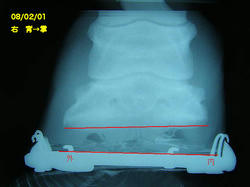

9月の右前肢

今回の右前肢

こちらも蟻洞がなくなりました。

順調に改善しているのが確認できて本当にホッとしました〜